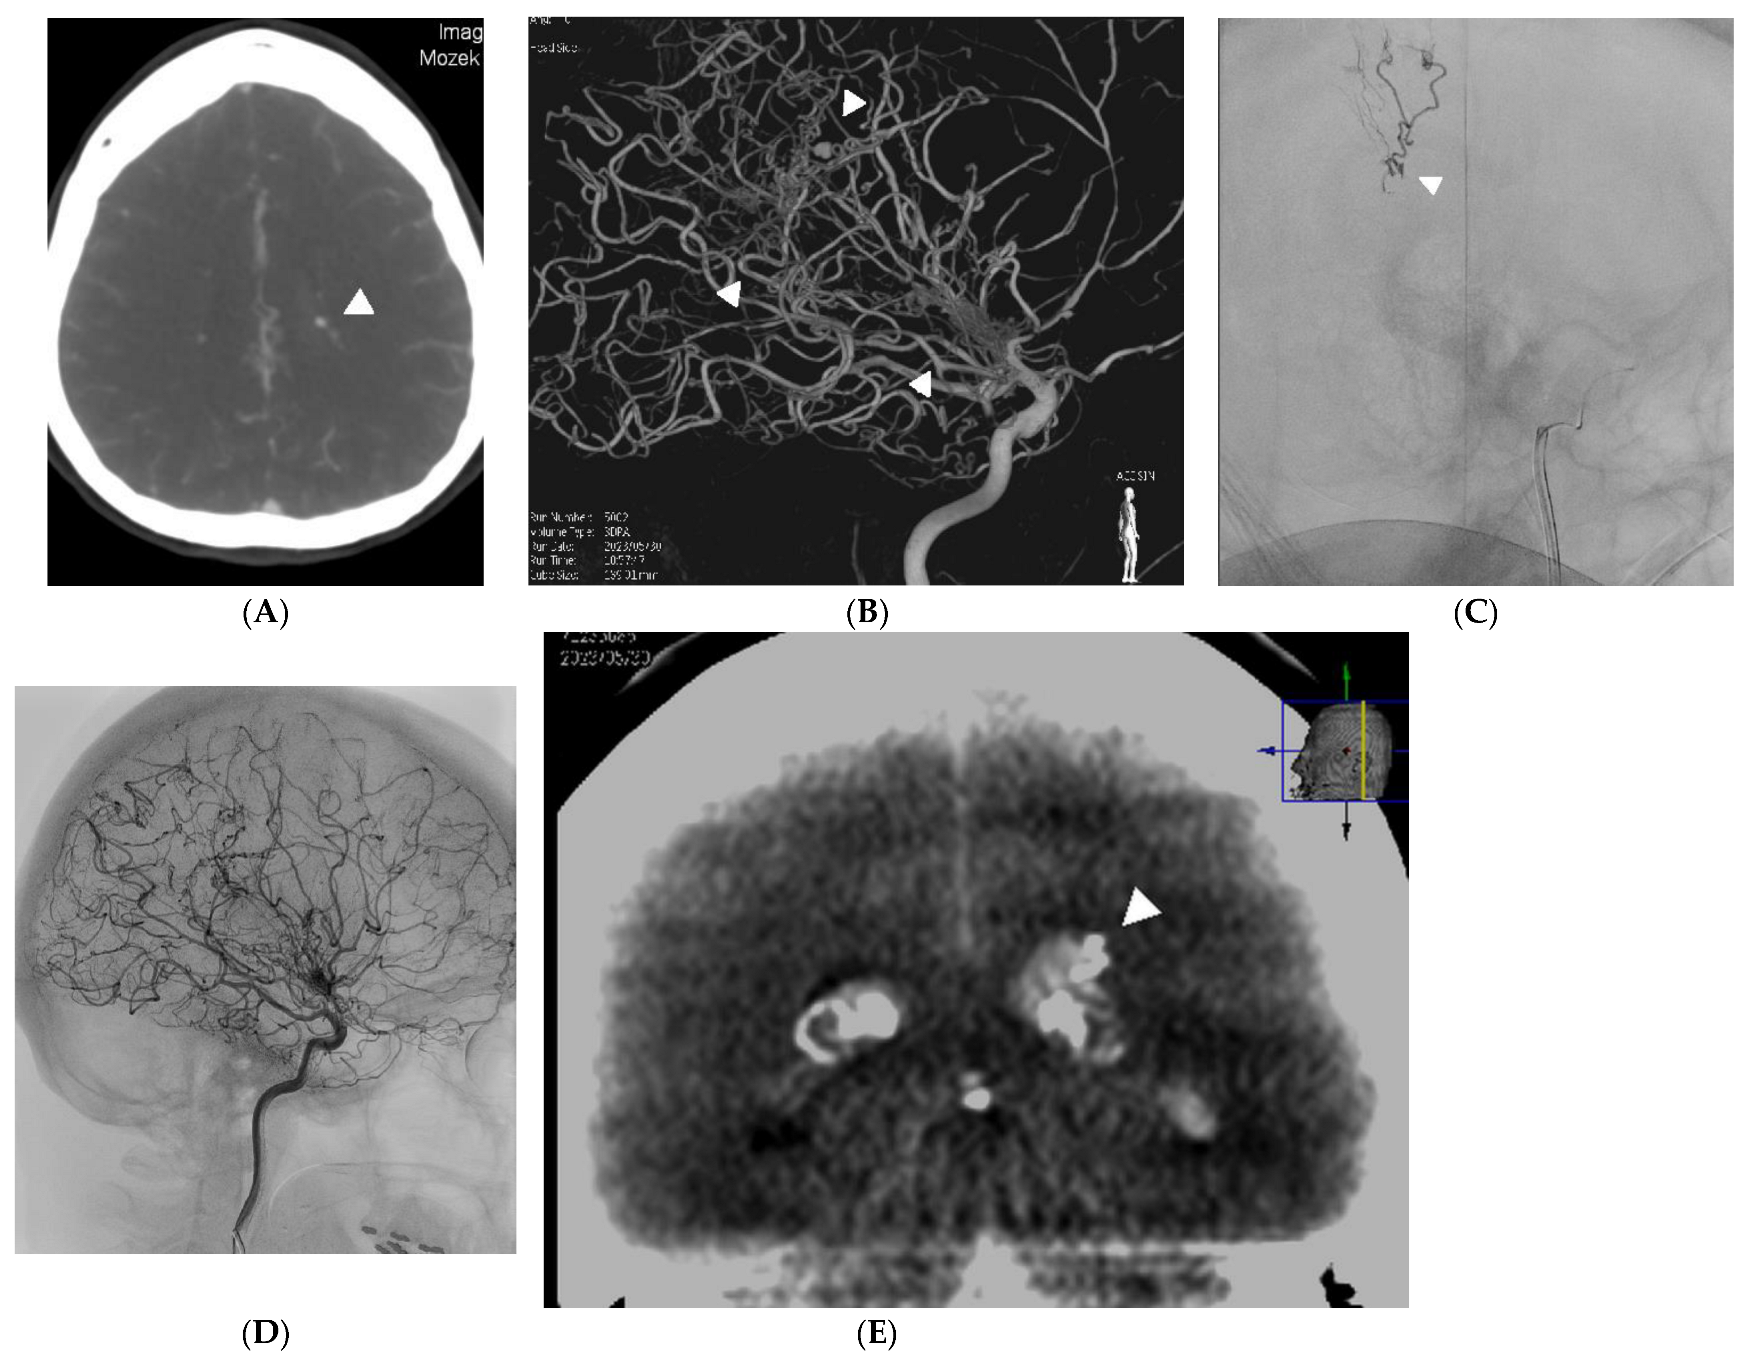

Endovascular Therapy of Ruptured Aneurysms on Moyamoya Collateral Vessels: Two Cases

2. Case Reports